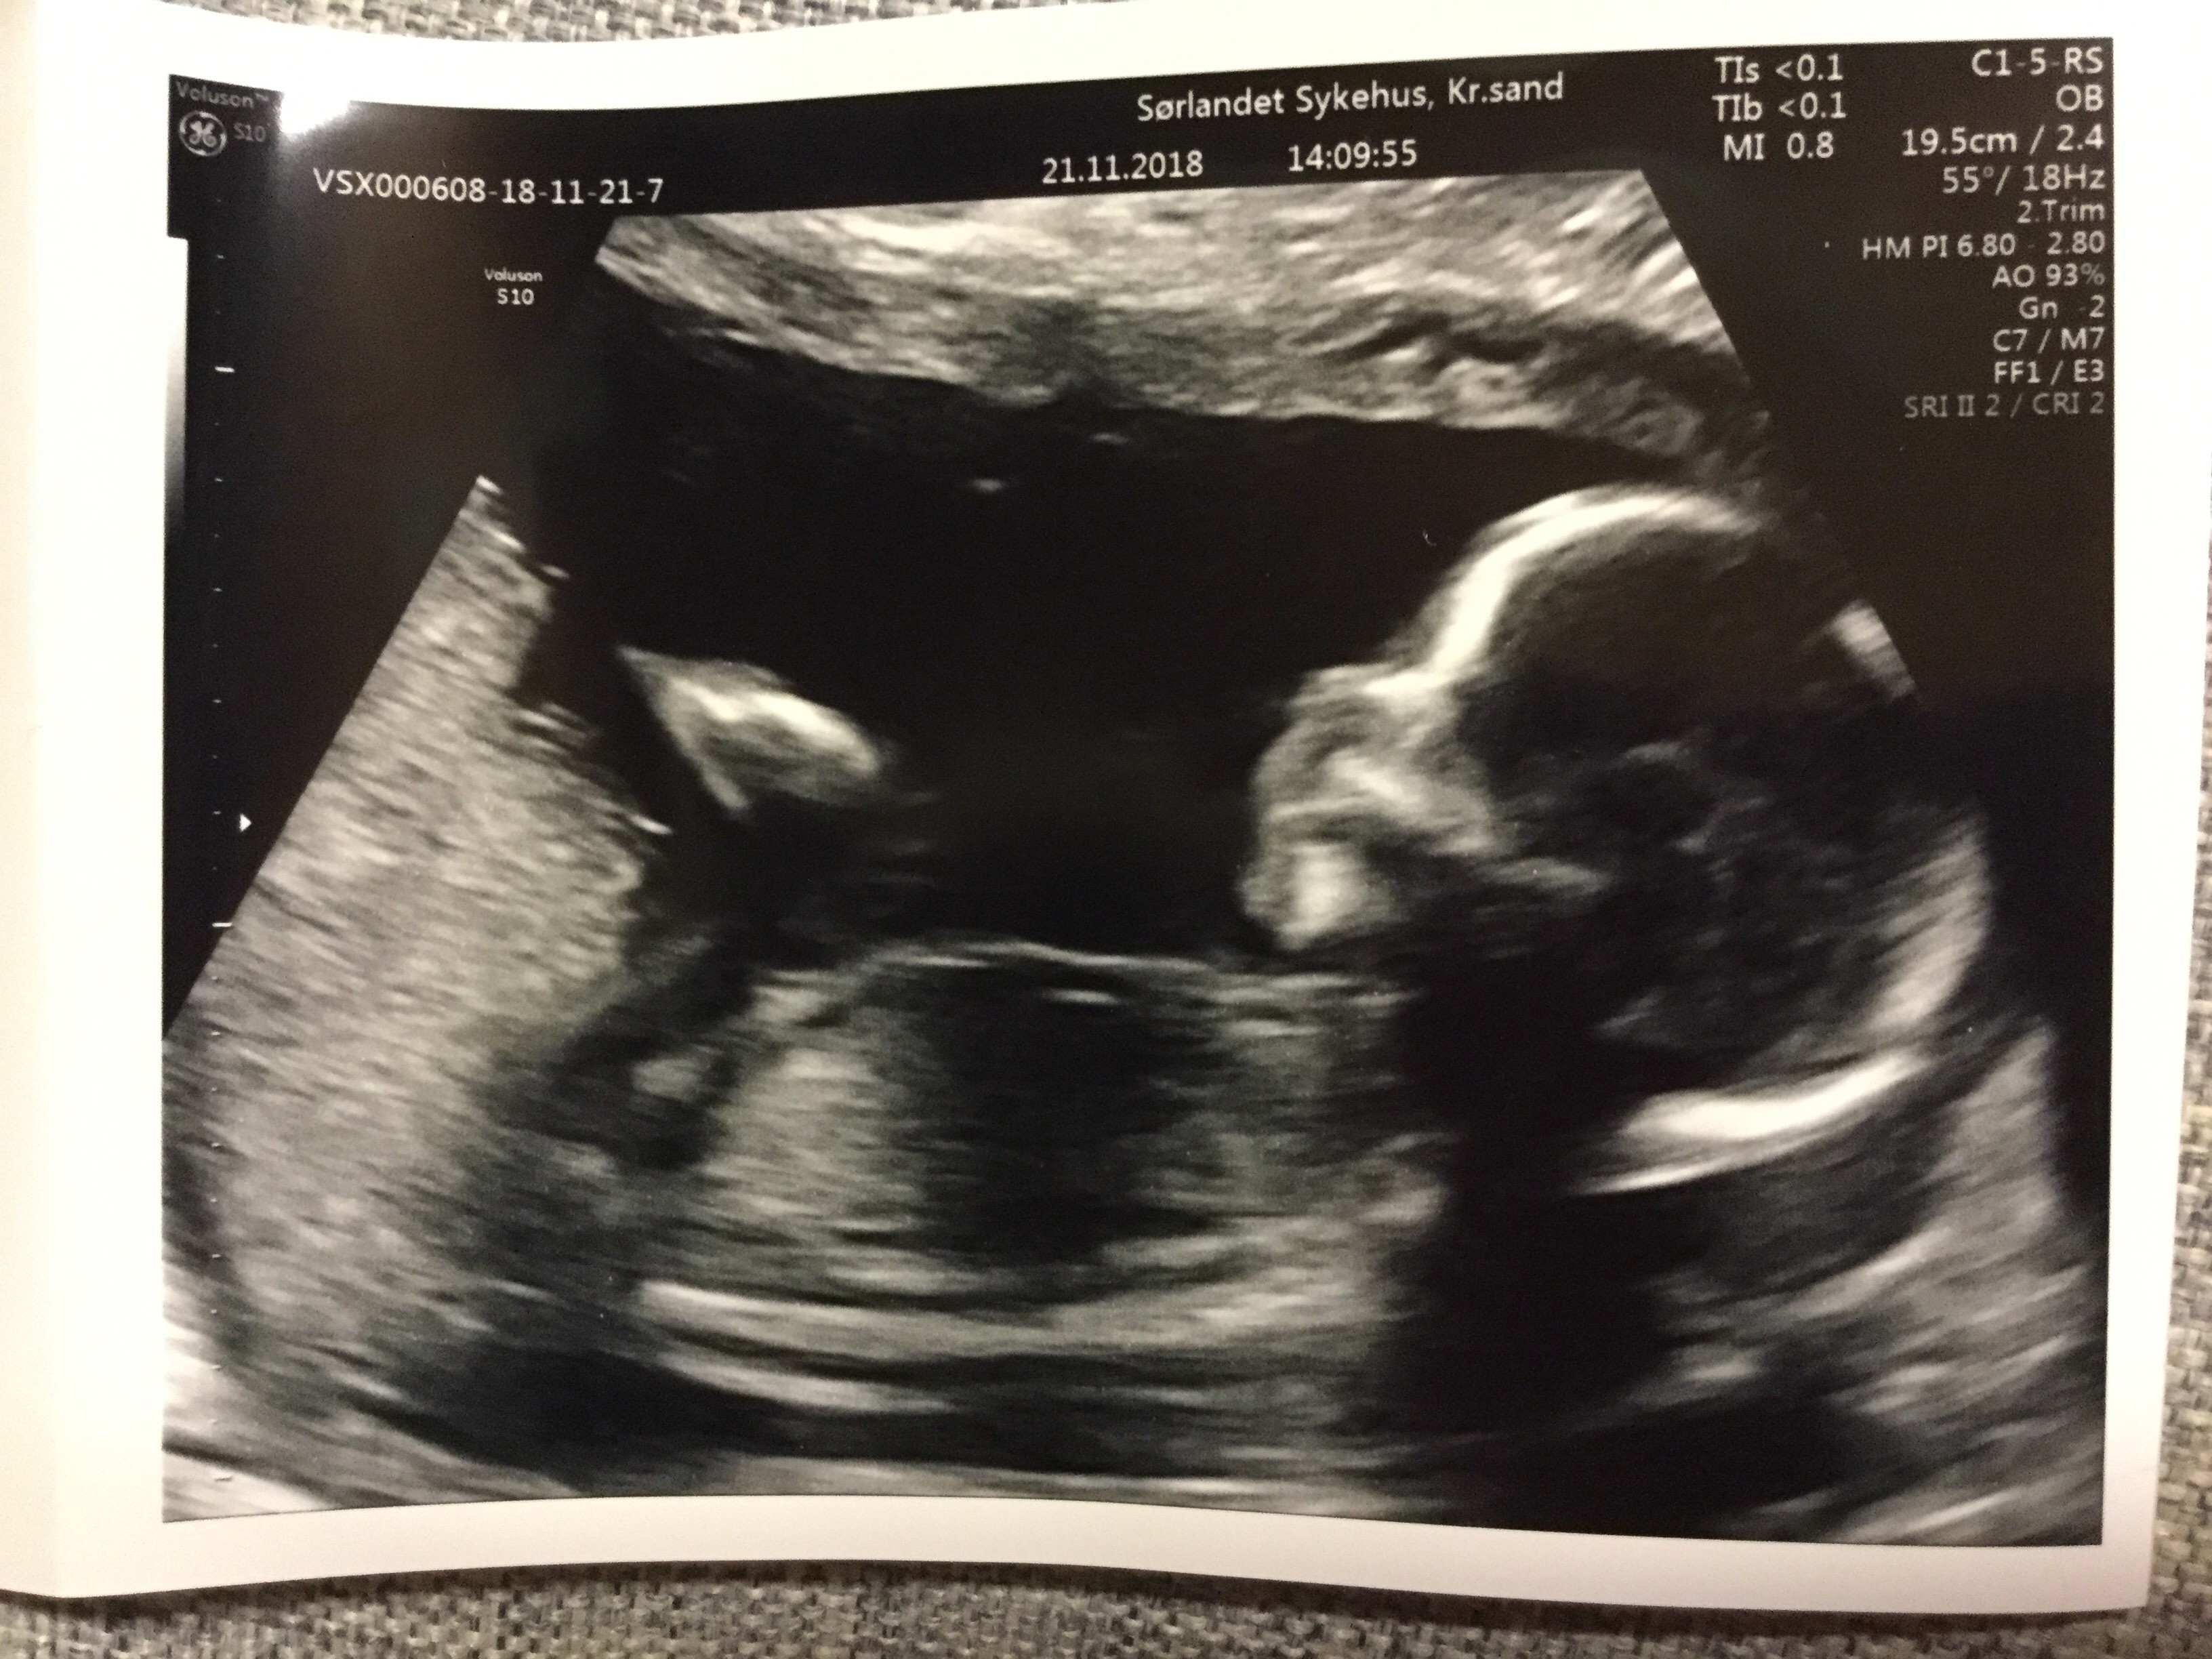

Tydzień ciąży wg om 19+6

Tydzień ciąży wg usg 19+5

Waga: 311 g

Tętno: 160 u/min

Płeć: dziewczynka

Narządy prawidłowe